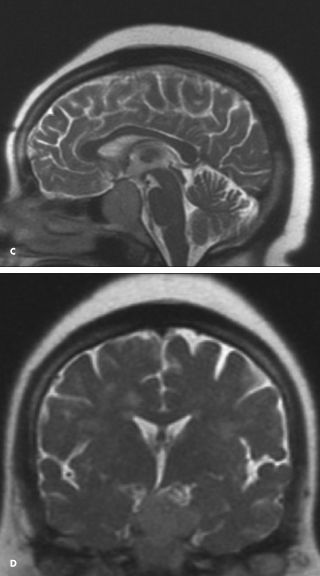

Pituitary MRI with gadolinium should be performed in all patients with ACTH-dependent Cushing’s syndrome.1,2 The patient’s MRI scan showed a 3.7 3 2.7 3 2.0 cm sellar mass with encroachment on the optic chiasm (C and D).

Cushing’s disease due to pituitary macroadenoma is uncommon and accounts for fewer than 4% to 10% of cases. Most cases of Cushing’s disease are the result of microadenomas, particularly tumors smaller than 6 mm, which can easily be missed on imaging studies. Therefore, in cases in which the results of clinical, biochemical, and radiologic studies are discordant or equivocal, bilateral inferior petrosal sinus sampling should be performed at a center with extensive experience in this procedure.